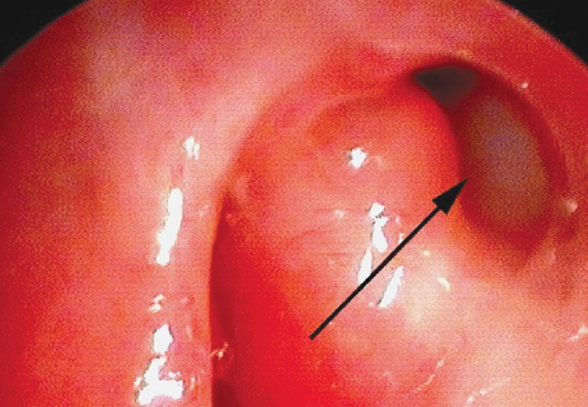

The following results were obtained. “Recovery” was noted in four patients and “improvement” in one, and the dacryostomy cicatrized in one patient. Figure 7 shows the endoscopic presentation of the nasal cavity 6 months after endonasal balloon plasty of dacryostomy.

Fig. 7. Endoscopic view of a dacryocystorhinostomy-ostium (left nasal cavity) 6 months after endonasal balloon dacryoplasty; arrow indicates the lumen of the dacryocystorhinostomy-ostium

Рис. 7. Эндоскопическая картина области дакриостомы (левая половина носа) через 6 мес. после эндоназальной баллонной дакриопластики; стрелкой указан просвет дакриостомы